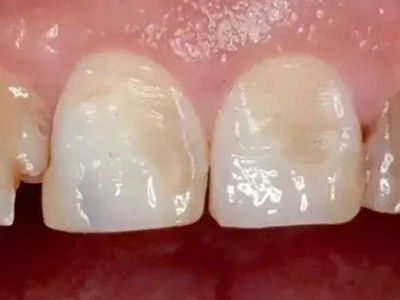

酸蚀症牙齿缺损表面凹凸不平图

酸蚀症可使牙齿表面出现缺损,两颗上门牙表面有局部凹陷,使牙面凹凸不平,质地硬且无明显颜色改变,该病可能是盐酸腐蚀牙齿导致。